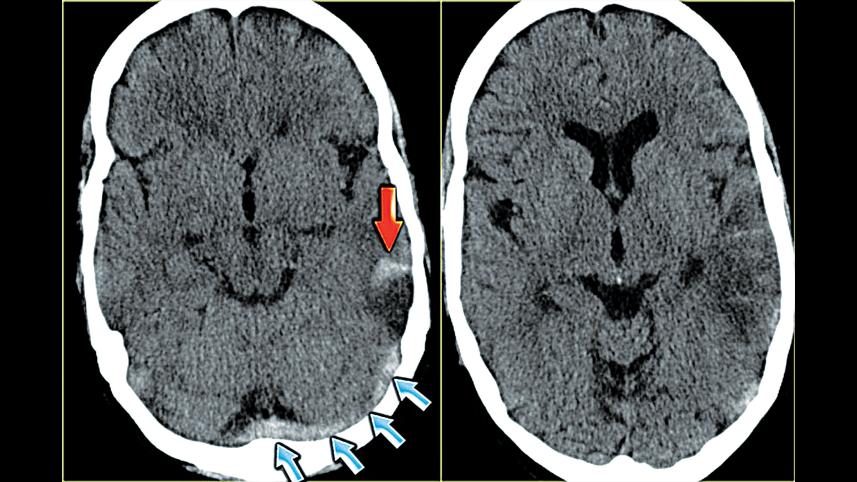

Rates of cerebral venous thrombosis (CVT), also called cerebral venous sinus thrombosis, are significantly higher among people with COVID-19 than in the general population or in mRNA vaccine recipients, suggests an unpublished study.